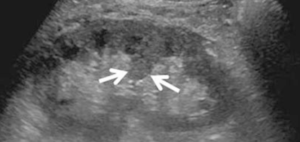

4-Extrarenal pelvis

هنا ببساطة يتواجد حوض الكلية خارج الكلية وكأنه كيس خارجي. الأهمية هنا تكمن في تمييزه بأنه تغير طبيعي وليس توسع في حوض الكلية أو كيس. التفرقة بينه وبين hydronephrosis تكون في عدم وحود توسع في calycis كما هو الحال في hydronephrosis.

في هذه الحالات يفضل التصوير بشكل transverse للتأكد.